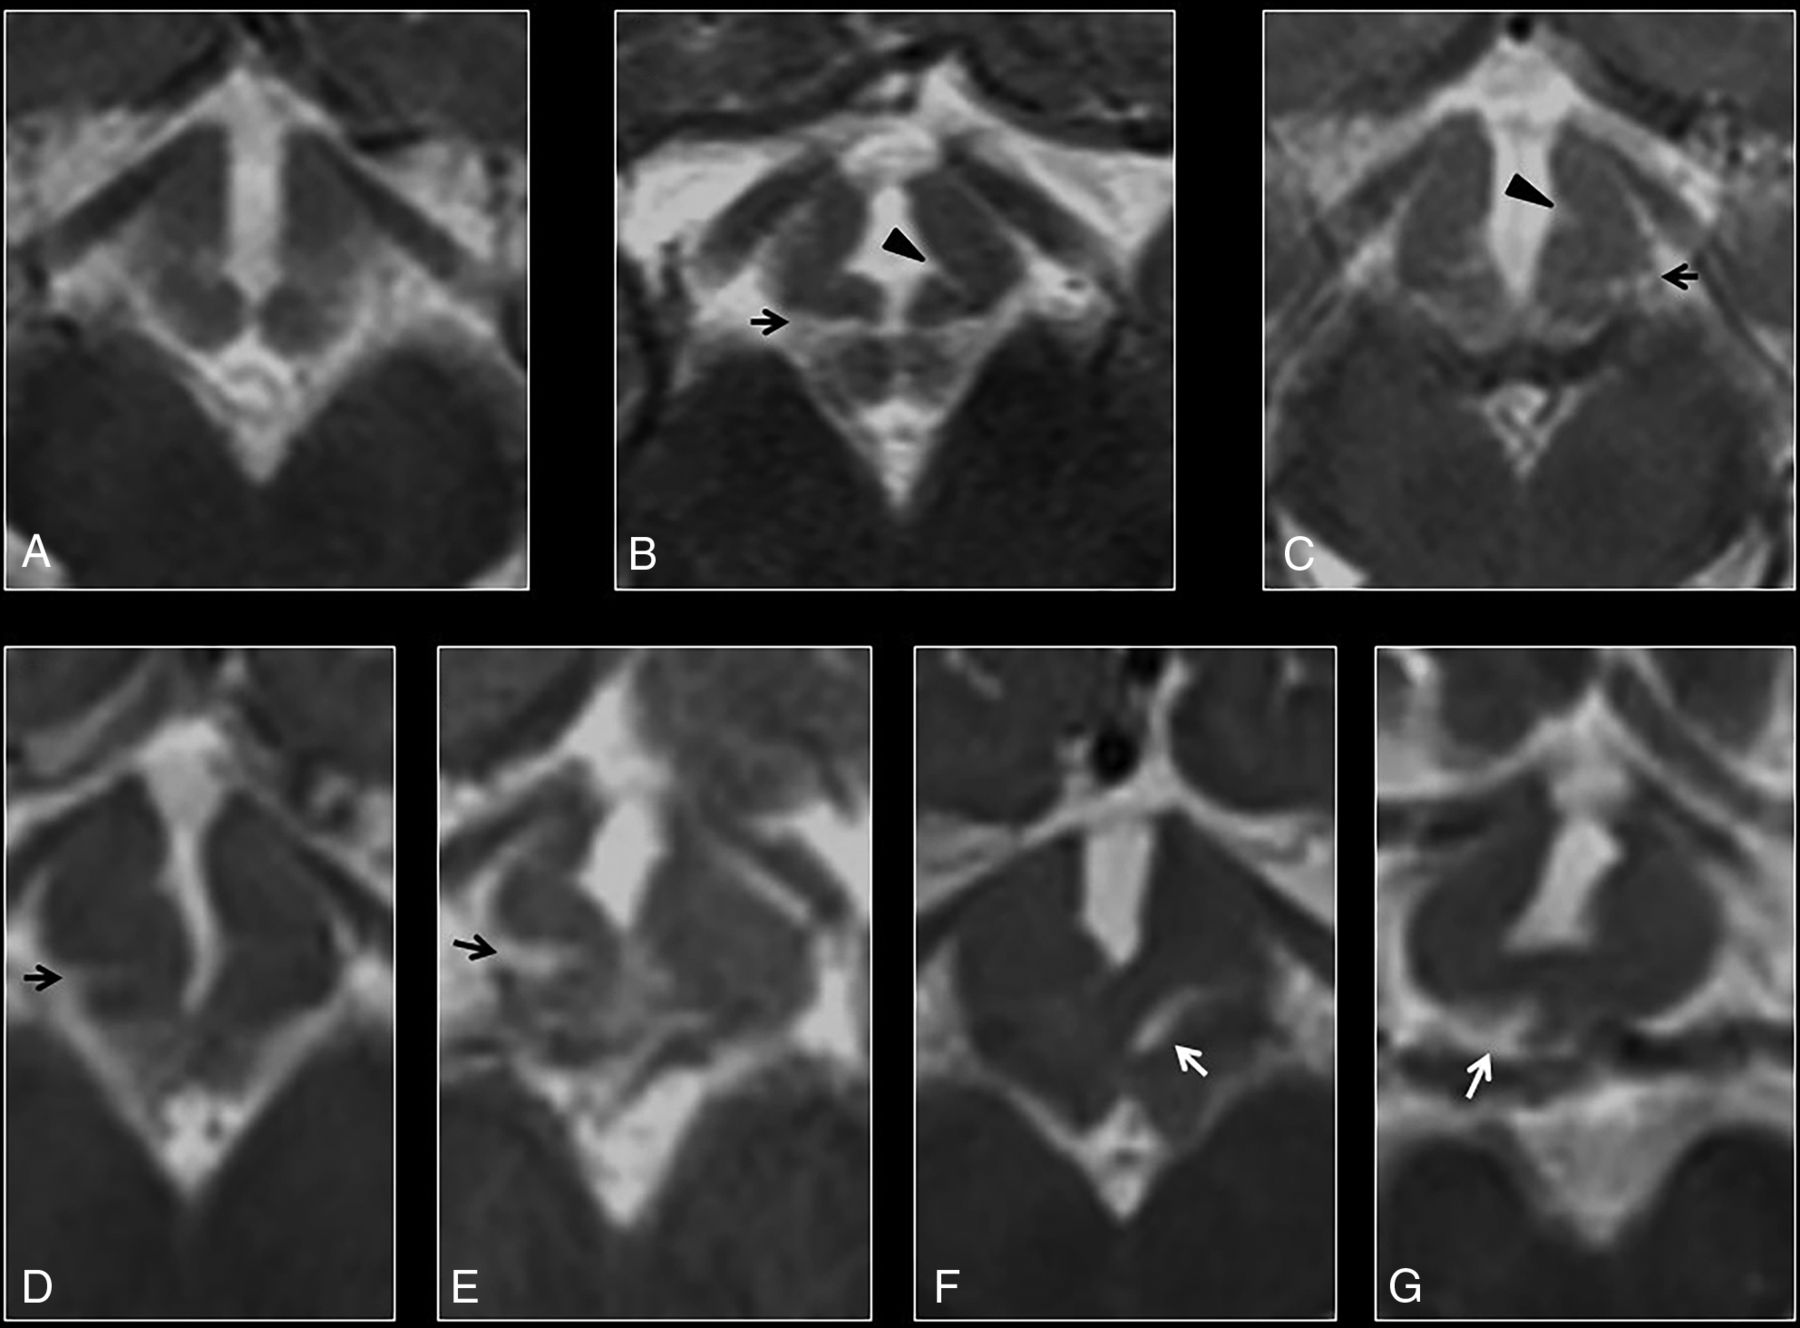

Coronal T2 morphology.

Six patients with DFNX2 showed concave morphology of the medial eminence in relation to the pituitary gland, with the lowest point of the ventromedial hypothalamus below the medial eminence (κ = 0.78). Two patients with DFNX2 showed convex morphology, and 2 had suboptimal images of the hypothalamus on the coronal plane (Fig 3A–C). None of the controls showed concave medial eminence morphology (P < .001). To further characterize the abnormal hypothalamic concavity on the coronal plane, we measured the coronal hypothalamic–septum pellucidum angle. The first component of this angle was a straight craniocaudal line along the septum pellucidum that crossed the vertex of the concave or convex medial eminence (Fig 3D, black line). The second component was another straight line originating from the previously mentioned vertex of the medial eminence to the most caudal end of the ventromedial hypothalamus; the angle between these 2 lines on either side was named the right and left coronal hypothalamic–septum angle, respectively. The right coronal hypothalamic–septum angle of patients with DFNX2 measured 115.5° ± 17.34°, while it measured 79° ± 8.05° in age-matched controls (P < .001). The left coronal hypothalamic–septum angle of patients with DFNX2 measured 113.87° ± 16.87°, while it measured 81.87° ± 9.32° in age-matched controls (P < .001). The individual intraclass correlation coefficient was 0.88 and 0.77 on the right and left sides, respectively.

A, Coronal T2 anatomy of a normal hypothalamus showing the classic convex morphology of the medial eminence. B–H, High-resolution coronal T2 images show progressive bending of the ventromedial hypothalamus (from mild to severe). B, High-resolution coronal T2 image shows abnormal concavity at the junction between the ventromedial hypothalamus and the medial eminence, with a low-lying ventromedial hypothalamus (black arrow) in relation to the medial eminence (ME). These findings show an abnormal concave morphology of the hypothalamus in relation to the pituitary gland. C, Coronal T2 FLAIR image of another patient with DFNX2, which demonstrates isointense signal compared with the adjacent globus pallidus. Note again the characteristic bending of the ventromedial hypothalamus and its caudal location in relation to the medial eminence (white arrow). D, Measurement of the angle between the tip of the ventromedial hypothalamus and the septum pellucidum (white arrows). E, Measurement of the craniocaudal length of the ventromedial hypothalamus at the lowest point (black arrow) in relation to the basal forebrain (horizontal line). The basal forebrain (white arrowheads) is also indicated on images A and D. F and G, In some cases, the low-lying hypothalamus and the folding are so severe that some hypothalamic segments appear masslike, though the overall appearance is in keeping with diffuse folding. H, Severe hypothalamic bending in a patient with DFNX2, which shows cranial folding of the hypothalamus (black arrow) apart from the typical low-lying or hanging infundibular nucleus (not shown in this image).

Another measurement was proposed to further characterize the hypothalamic concavity and low-lying ventromedial hypothalamus: the craniocaudal length between the basal forebrain and the lowest point of the ventromedial hypothalamus. The first component of this measurement was a straight line over the inferior edge of the basal forebrain (Fig 3E, white arrowheads), and the second component was a perpendicular line linking this line with the lowest point of the ventromedial hypothalamus on either side (Fig 3E, black arrow). The right forebrain-hypothalamus length in DFNX2 was 7.15 ± 3.02 mm, while it was 4.26 ± 0.7 mm in age-matched controls (P < .001). The left forebrain-hypothalamus length in DFNX2 measured 6.9 ± 2.1 mm, while it was 4.21 ± 0.73 mm in controls (P < .001). The individual intraclass correlation coefficient was 0.92 and 0.87 on the right and left sides, respectively.

On coronal T2 images.

A concave morphology of the medial eminence in relation to the pituitary gland with the lowest point of the ventromedial hypothalamus below the medial eminence (Fig 3) also showed high specificity and sensitivity (SE, 100%; SP, 97.1%). Furthermore, 2 measurements could help distinguish DFNX2 hypothalamic malformations from features in healthy patients: at least 1 hypothalamic-septum angle of ≥90° (SE, 90%; SP, 72.5%) as well as 1 forebrain-hypothalamic craniocaudal length of ≥6 mm (SE 70%; SP 79.7%). The presence of at least 3 abnormal variables was sufficient to rule out a normal hypothalamus (Table).